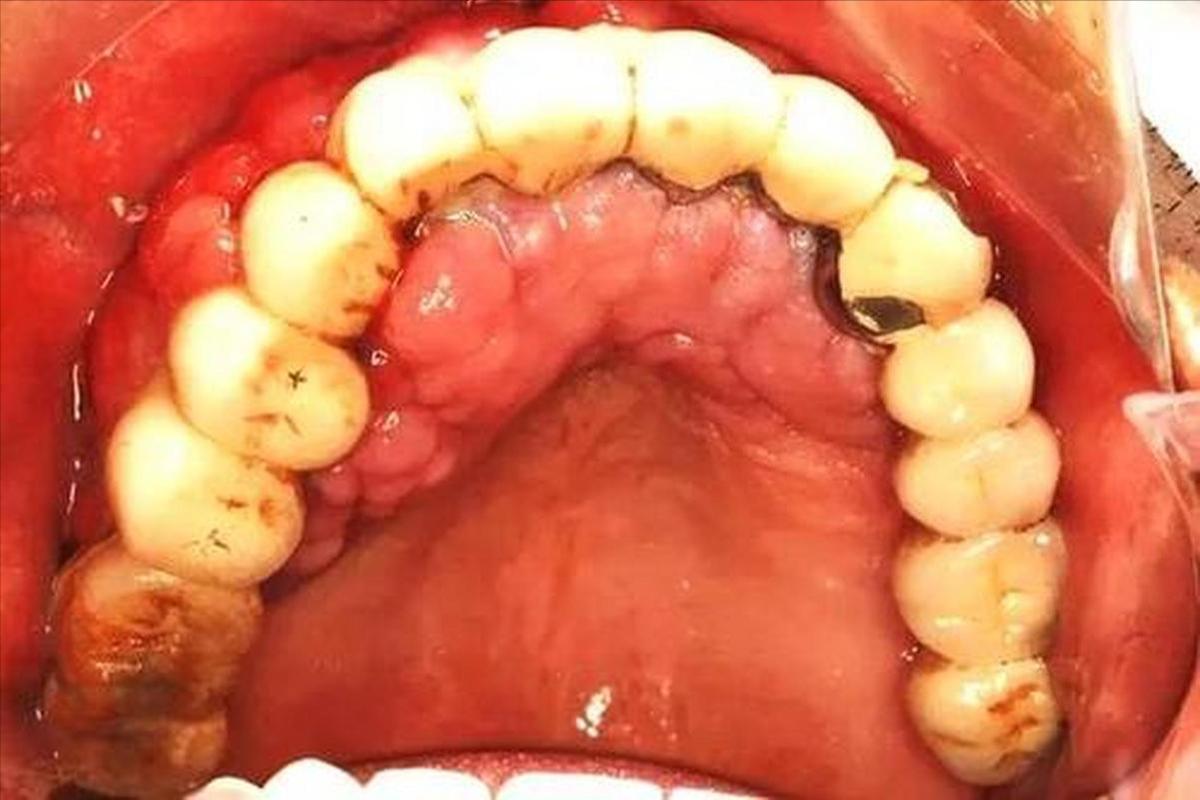

Finally, let's talk about the third symptom: bleeding gums. When brushing your teeth in the morning, if you notice bleeding gums and a strong, unpleasant odor in your mouth, don't just assume it's an oral health issue. Aside from problems within the mouth itself, this could also be a sign of liver dysfunction. The liver plays a crucial role in our body’s blood clotting function. If the liver is not functioning well, blood clotting can be impaired, making the gums prone to bleeding. It's like building a house—if the foundation isn't solid, the structure is likely to have issues. Similarly, our body's clotting function relies on the liver as its "foundation."